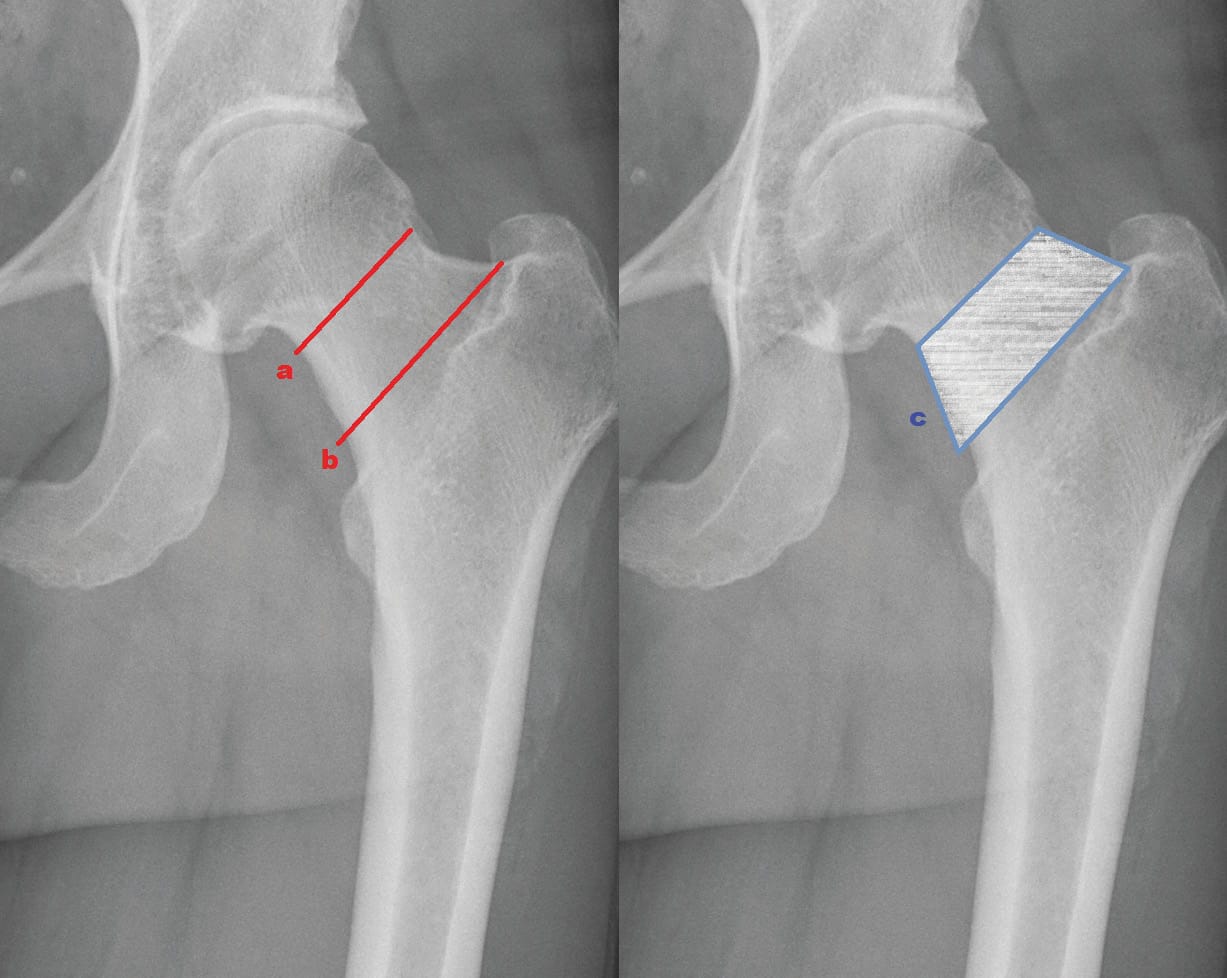

The clinical contributions in this issue address personalized alignment in TKA and examine why individualized TKA facilitates the restoration of native alignment, alongside current concepts and a glimpse into the future of partial knee replacement. A new perspective in cementless total knee arthroplasty broadens the implant discussion, while individualised therapy of femoral neck fractures — the Wiesbaden concept extends the scope to proximal femoral pathology.